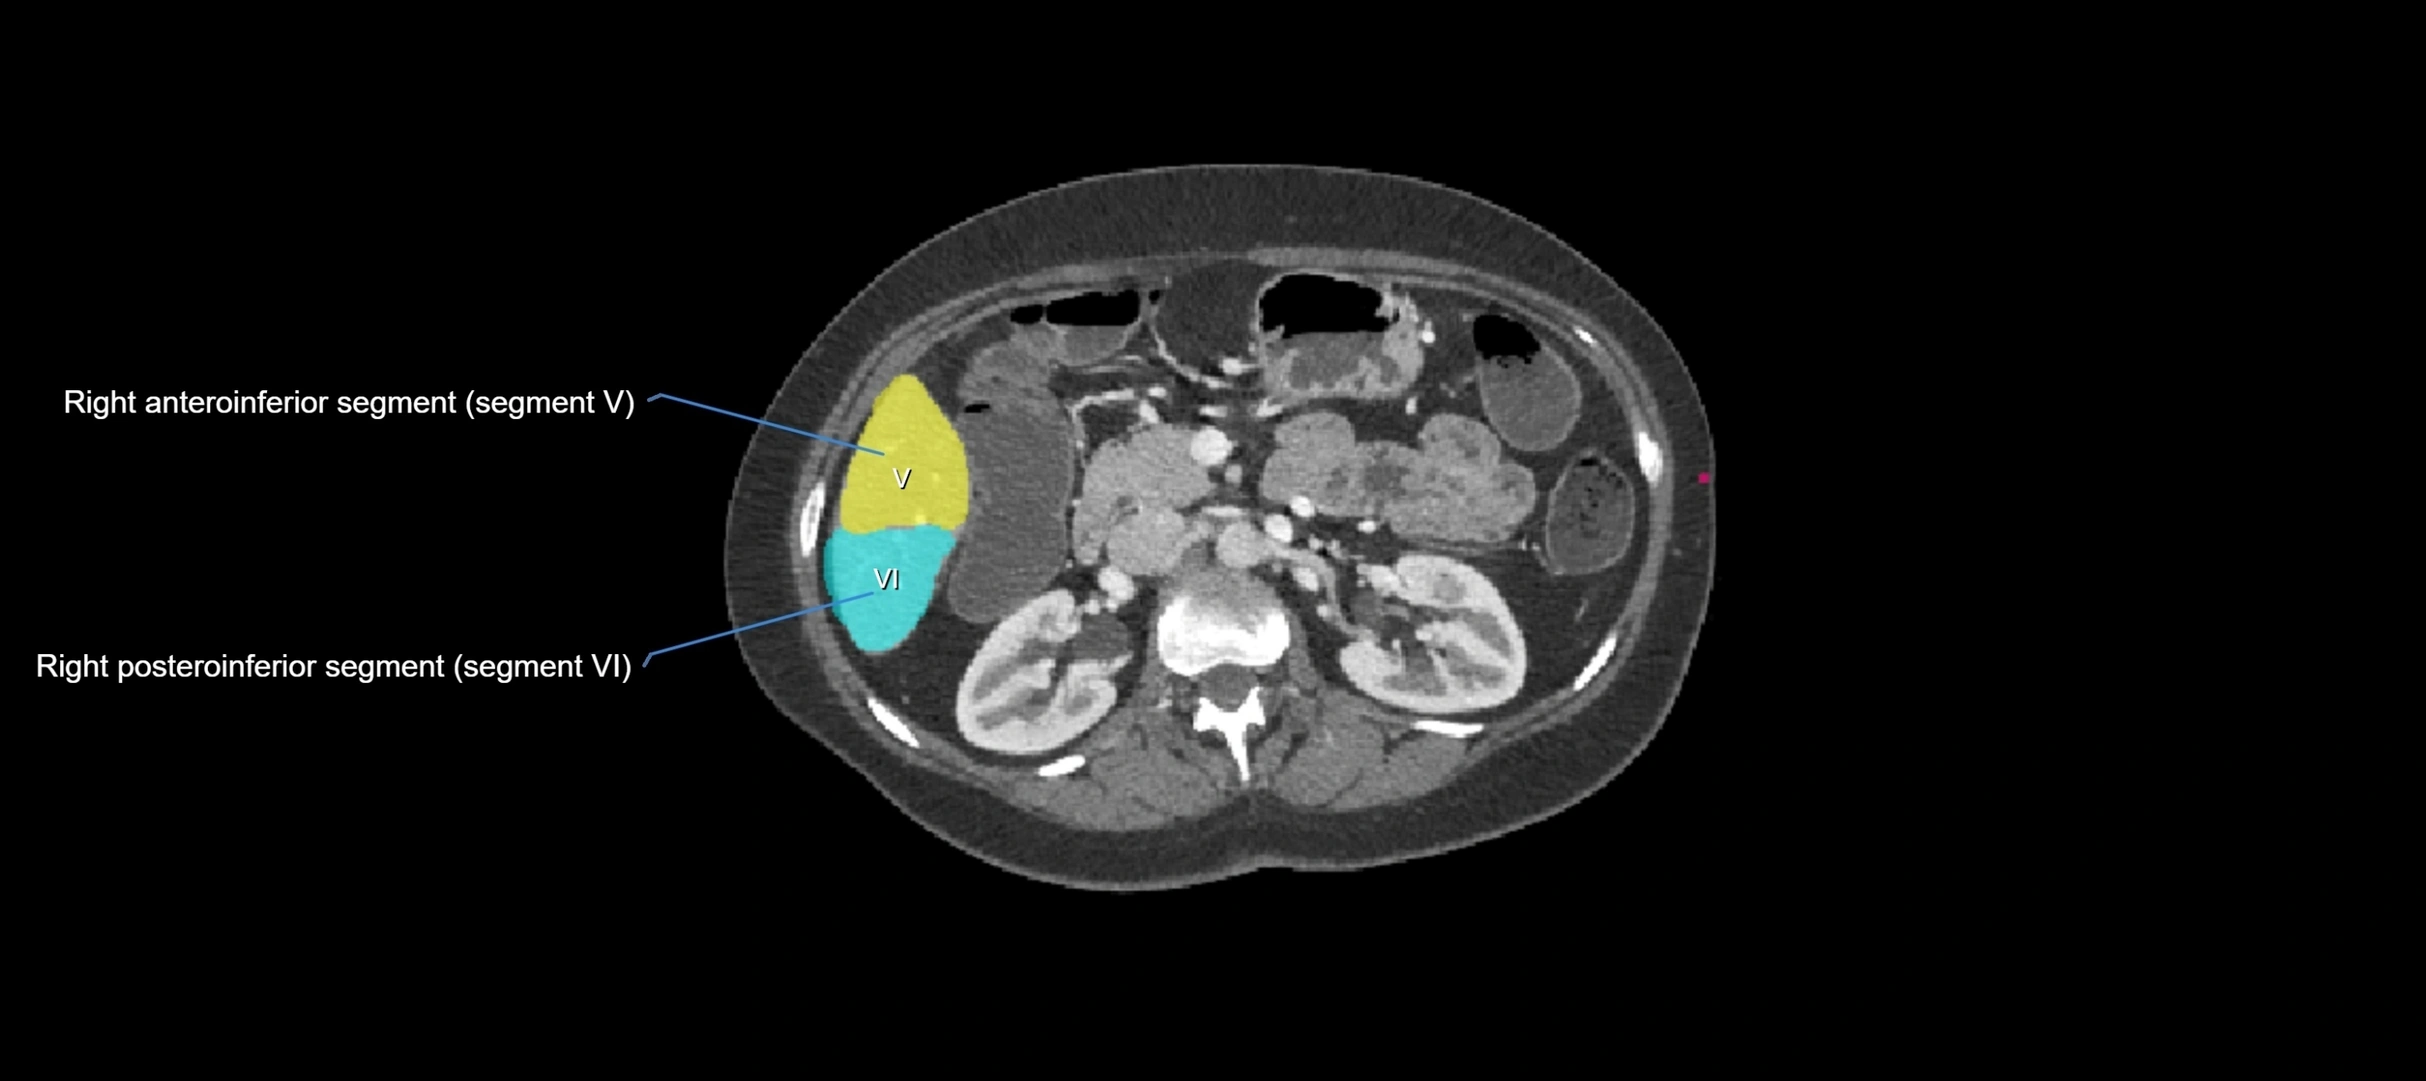

CT Appearance

CT Pre-Contrast:

• Caudate lobe appears as a soft-tissue density, isodense to the rest of the liver

• Enlargement may be appreciated in cirrhosis or Budd–Chiari syndrome

CT Post-Contrast:

• Homogeneous enhancement in the portal venous phase, similar to rest of liver

• Independent venous drainage into the IVC may be visualized

• Lesions follow characteristic CT enhancement patterns (HCC: arterial hyperenhancement with washout; hemangiomas: peripheral nodular enhancement with centripetal fill-in)

CT Venous Phase (functional significance):

• Caudate lobe often enhances relatively more than other lobes in Budd–Chiari syndrome, due to preserved venous outflow